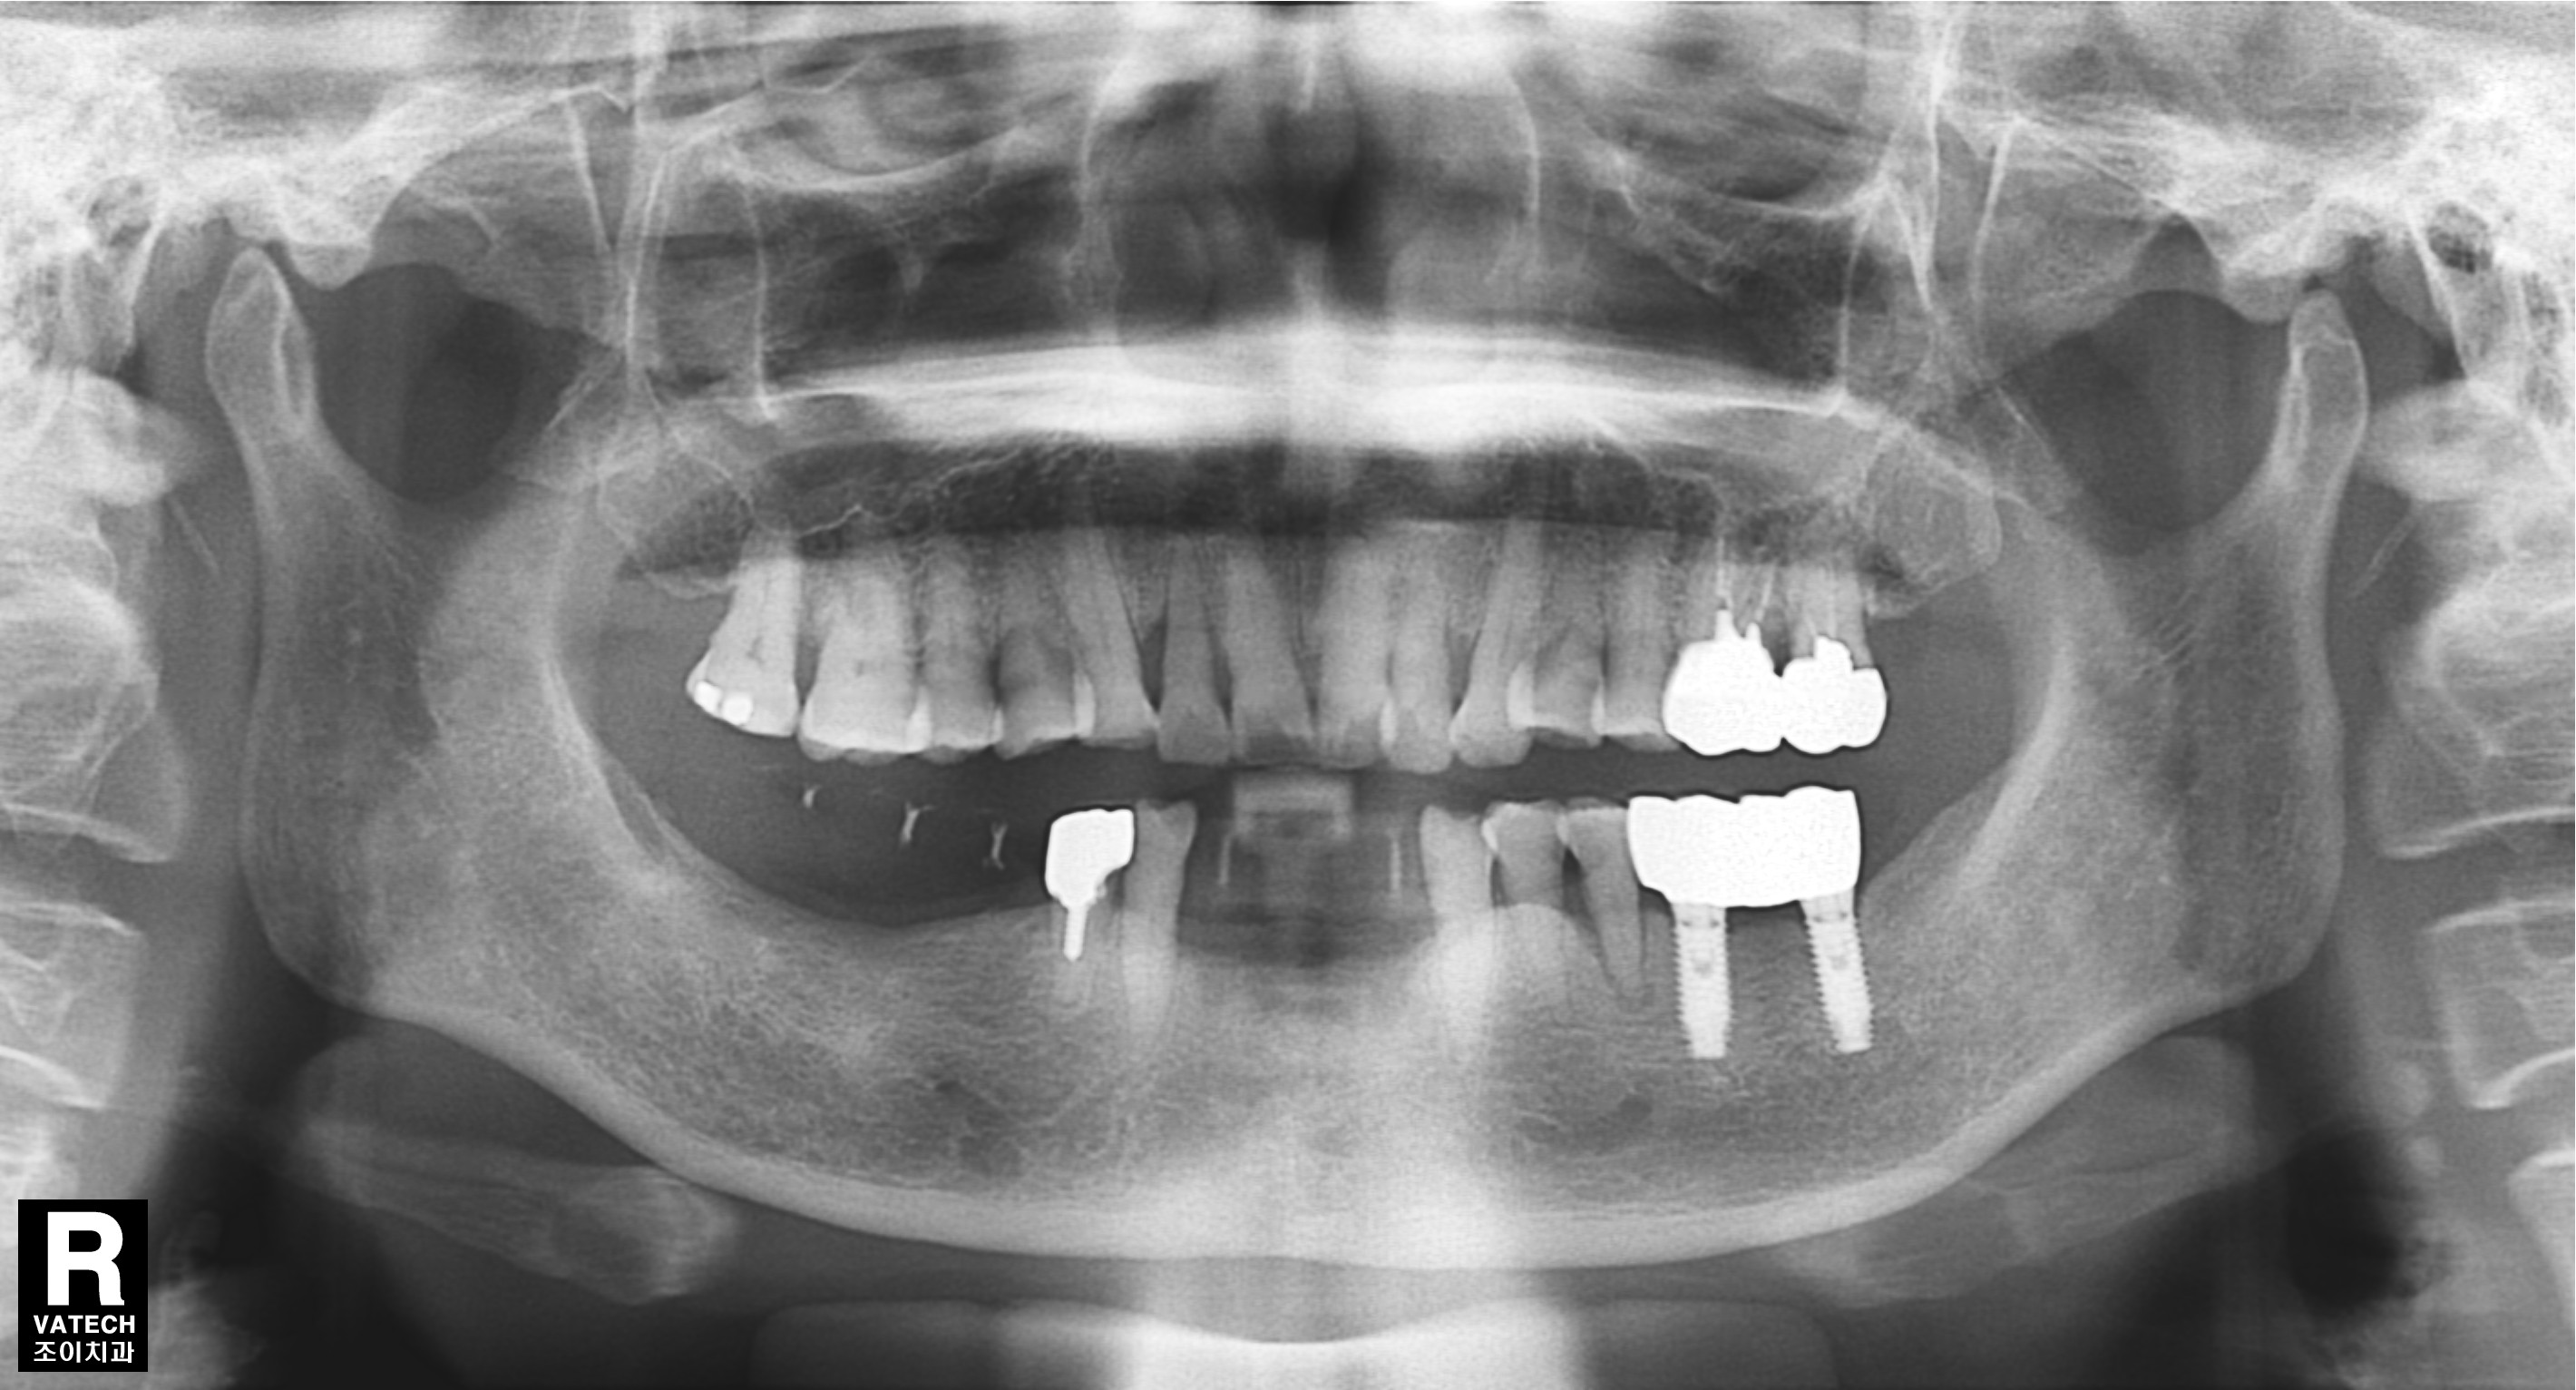

[임플란트] 제목 : 하악전치

임플란트 보철